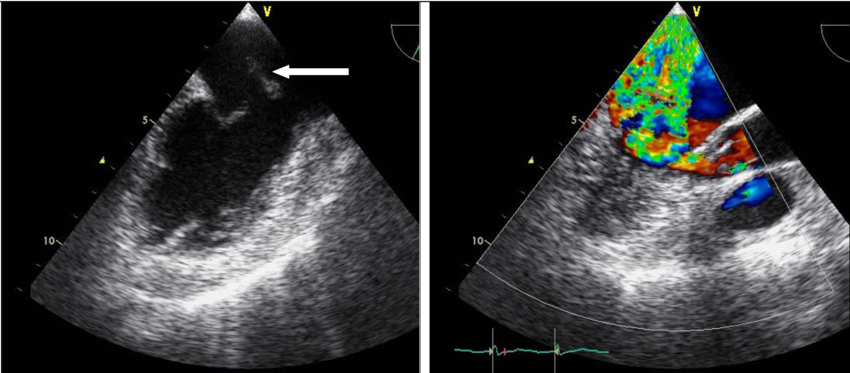

Чреспищеводная ЭхоКГ: стрелкой показано пролабирование передней створки митрального клапана с папиллярной мышцей в полость левого предсердия